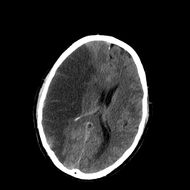

INFARCT.jpg

CT scan slice of the brain showing a right-hemispheric ischemic stroke (left side of image).